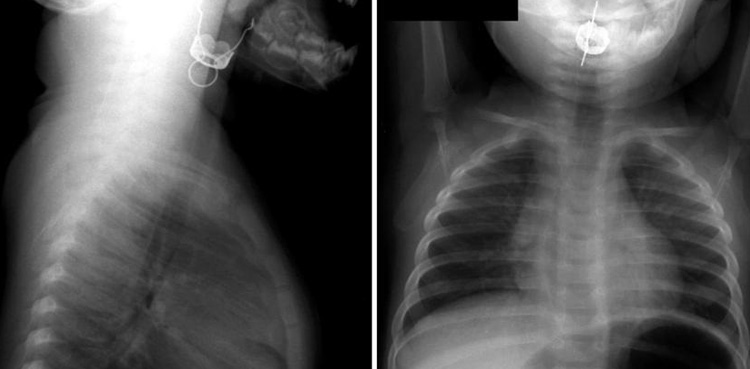

An Australian pediatric nurse Sarah Hunstead, owner of the children’s safety page called CPR Kids, on her social media platform, posted some horrifying X-rays of the festive ornament that was stuck in the child’s throat.

On her Facebook page, Hunstead wrote that “Christmas is an exciting time, but it can bring some specific holiday season hazards. This unbelievable image shows a part of a Christmas bauble swallowed by a toddler”.

“Thankfully, there was just enough air space for the little one to breathe until it was removed, while It’s easy to forget baby-proofing the temporary seasonal additions around the home, even if you are usually on top of proofing all the things,” she added.